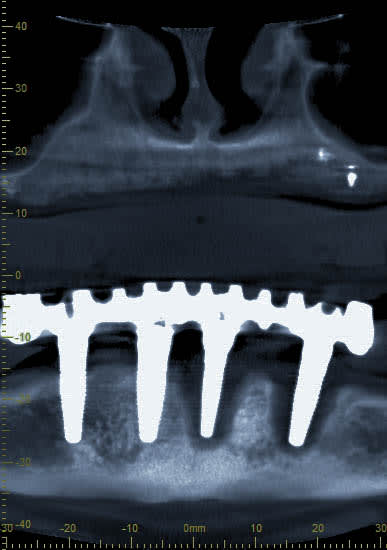

Tu veux dire que désormais, avec la perte de deux implants contigus avulsés pour cause de péri-implantite, le all on four est transformé en all on two?

pose des implants par un praticien de Metz il y a10 ans. aucun problème particulier.

pratiquement aucune visites en 10 ans ...

la patiente est venue me consulter car elle souhaité la même chose au maxillaire. c'est là que j'ai découvert le pot aux roses il y a 3-4 semaines.

je lui ai dit que pour moi il était urgent de virer les implants et de prévoir une reconstitution osseuse au plus vite.